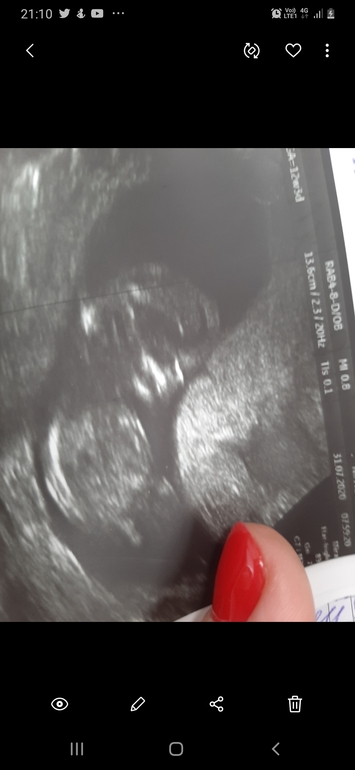

Кто в животике? Фото узи 12 недель

Пол малышаПока я пол не знаю но судя по узи у других девочек, если пол мужской то бугорок вверх. А если женский то параллельно позвоночнику.

Ведь по этому УЗИ больше на девочку похоже?

Точный результат будет через неделю

Да, вроде не бугорок... Может все таки девченка? Мо методу Рамзи вам кого нагадали?

🤭🤭🤭 а я думала что вот этот отросток и есть. А покажите бугорок мне у других

На вашем фото это либо пуповина, либо нога.. Я конечно не эксперт, но мне кажется это не бугорок. Вот нашла фото где его видно: просто черточка